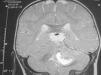

Las crisis no respondieron a diazepam, fenitoína ni valproato por vía intravenosa ni a valproato oral. Con carbamazepina por vía oral los episodios disminuyeron en frecuencia y duración, pero a los 9 meses se añadió un tortícolis indoloro. Una nueva RM cerebral, 5 meses después de la inicial (que revisada a posteriori no muestra ninguna alteración) y tras 1 mes de tortícolis persistente, mostró una tumoración de la fosa posterior (fig. 1). A los 11 meses se realiza una resección subtotal de meduloblastoma con posterior quimioterapia sistémica e intraventricular.